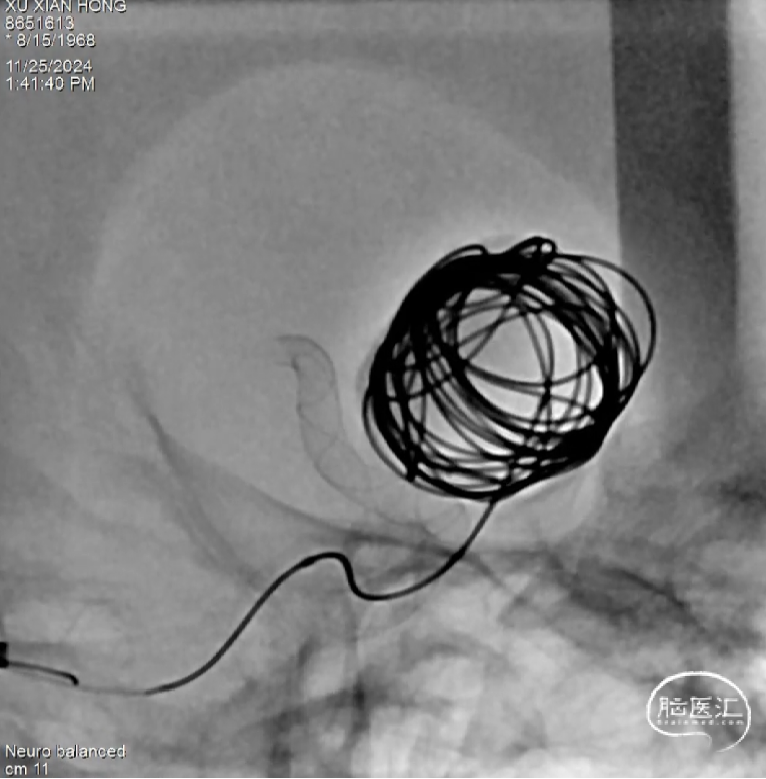

Step8:术后即刻工作位造影,可见瘤颈部位及囊内血流滞留明显,支架打开、贴壁良好。

术后检查

术后即刻正侧位造影,动脉瘤滞留明显、远端血流通畅。

正位造影

侧位造影

术后体会

Tubridge Plus“两维3D、全程显影”特点 ,极大提升了颅底部位的可视性、更好地判断支架打开和贴壁的情况。

Tubridge Plus通过结构优化,实现了支架与血管壁的无缝贴合和卓越的血流导向作用。相比上一代径向支撑力有所提升,打开/贴壁更加容易;同时采用0.027inch支架导管输送,简化了操作步骤,推送阻力下降。

表面采用BlueSilk Surface技术,降低血栓附着,我们期待后期随访的效果。